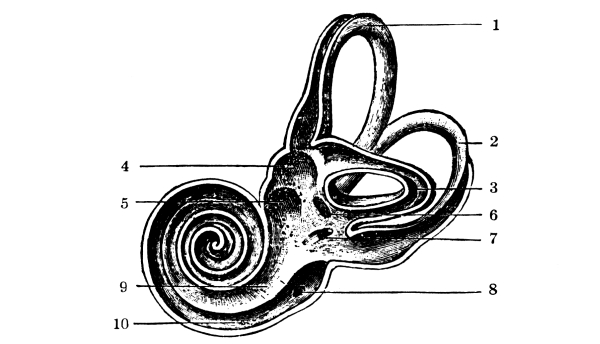

The Nose, 57—The Sense of Smell, 58—The Mouth, 59—The Hyoid Bone, 60—The Teeth, 60—The Sense of Taste, 61—Salivary Glands, 61—The Tonsils, 62—The Ear, 63—Eustachian Tubes, 63—Sensation of Hearing, 65—The Eye, 66—Lachrymal Gland, 68—Coats of the Eye, 68—Light Rays and Sight, 70—Accommodation, 72—Color Perception, 73. |